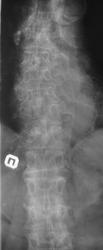

А реально это множественные патологические переломы позвонков разной степени, на фоне минералопении. А о ее природе мы можем только догадываться, вплоть до миеломы или даже метастатического поражения - тут нужны детальная клиника и анамнез...

Наиболее вероятно - дискормональная спондилопатия.

Ещё артроз рёберно-позвонковых суставов.